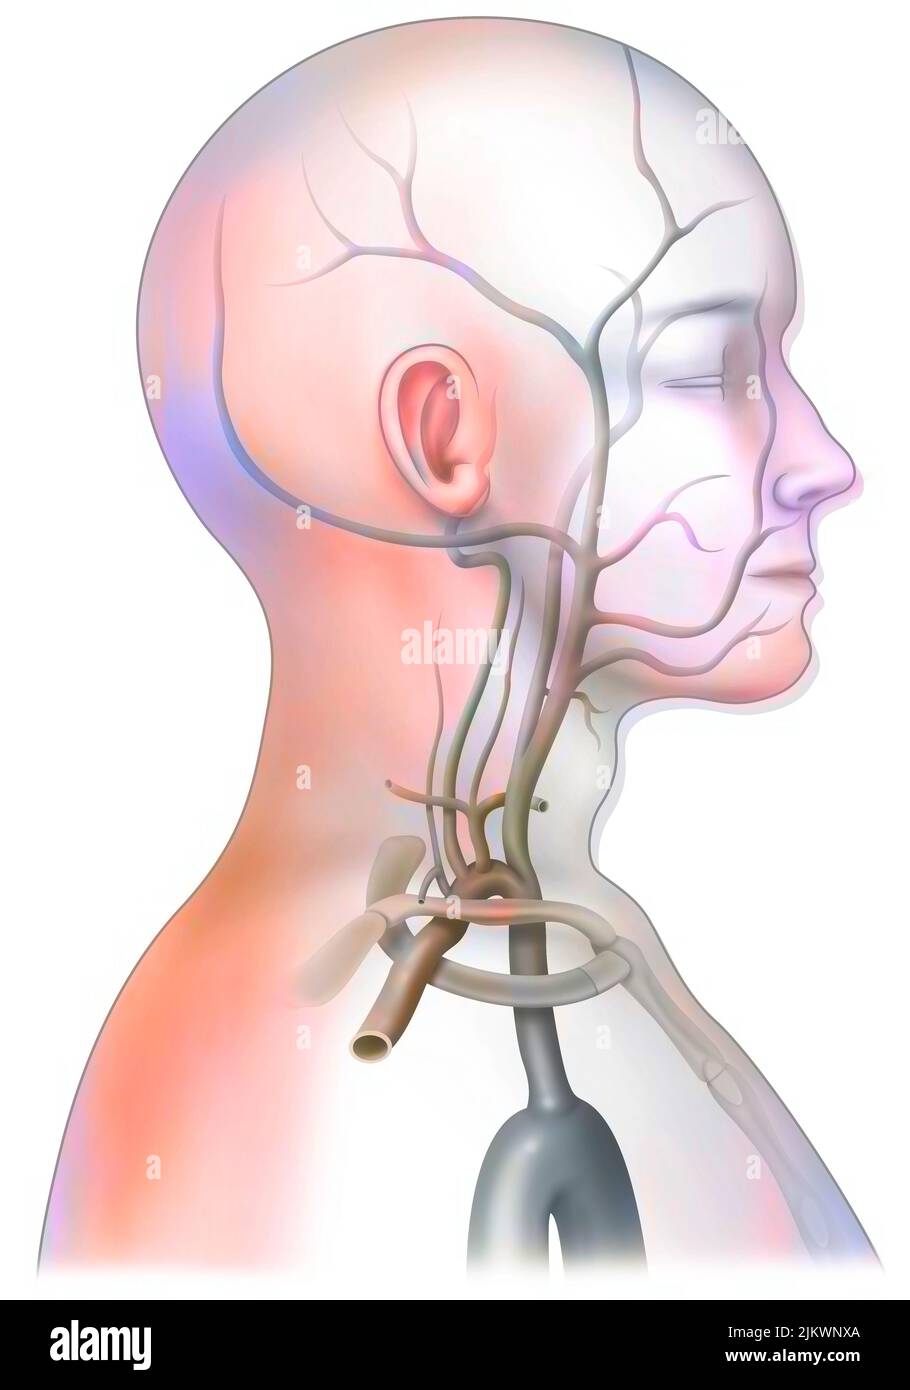

RF2JKWR03–Action des sels minéraux et des vitamines sur la transmission des impulsions nerveuses aux synapses.